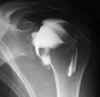

Letsels aan pezen en/of ligamenten van het gewricht |

Letsels van het gewrichtskapsel |

Ontwrichting |

Bot of kraarbeenletsels |

Gewrichtsmuizen (dit zijn kleine stukjes bot die los in

het gewricht voorkomen) |

Eventueel ontkleden van de punctieplaats, zoals

schouder, heup, ... |

Voor het inspuiten van het contrast wordt er best een

foto genomen van het te onderzoeken gewricht. |